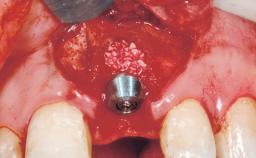

A 30-year-old female patient had lost tooth 21 and was referred to our clinic for consultation and treatment. Due to advanced apical infection, tooth 21 had been extracted two months earlier at another clinic and an acrylic-resin tooth had been bonded to the adjacent teeth. The patient desired implant treatment to avoid any damage to the adjacent natural teeth. While the patient had no history of any systemic disorder, she was a heavy smoker and exhibited medium to advanced periodontitis in the entire jaw. After the initial treatment to achieve a pocket probing depth of less than 4 mm and no bleeding on probing, a decrease in the height of the papillae mesial and distal to the extraction site and overall gingival recession were observed.

Type of Implants One-Piece|Reduced-Diameter

Bone Augmentation Horizontal|Staged

Augmentation Materials Autogenous chips|Membrane

Soft Tissue Grafting Simultaneous

Placement Protocol Early or late implant placement

Bone Volume Deficient horizontally, requiring prior grafting